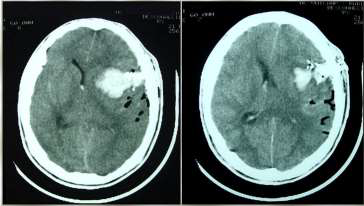

Caso clínico 3 para as questões 27 e 28.

Criança feminina, 04 anos, é encaminhada de Unidade de Pronto Atendimento (UPA) de Olinda-PE com história de cefaleia acompanhada de vômitos, inapetência e sonolência há 03 dias, sendo solicitado parecer da neurocirurgia. Ao exame: ECG Pediátrica de 13 (Resposta Ocular = 3 + Resposta Verbal = 4 + Resposta Motora = 6), isocórica e RFM lentificado bilateralmente, mobilizando todos os membros e reflexos presentes e simétricos.

Seguem, abaixo, as imagens de TC de crânio sem e com contraste da paciente, com índice de Evans de 0,41.

Pelas imagens mostradas, qual o mais provável diagnóstico e o objetivo do tratamento para a paciente?

Como se calcula o índice de Evans que foi de 0,41 e o que se fazer pela urgência nesse caso, respectivamente?